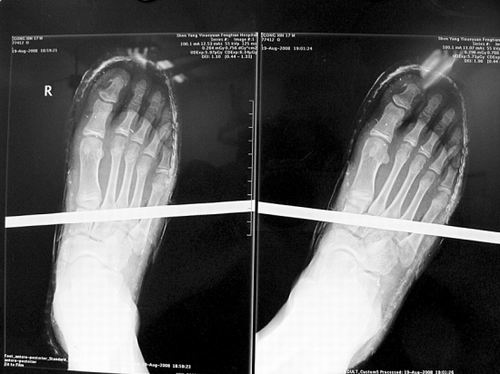

X光片顯示無大礙

事發(fā)時男孩穿著一雙布鞋,骨外二科陳賓醫(yī)生操起剪刀,將布鞋一塊塊剪掉。經(jīng)X光透視,醫(yī)生驚奇地發(fā)現(xiàn):男孩雖然被鋼筋穿透了右腳,但骨頭、大的血管和神經(jīng)都沒受任何傷害!

20日,記者從X光片子上看到,鋼筋避開了男孩腳掌骨頭密集的部位,而是從腳弓處穿過,這個部位基本上以軟組織為主!罢鏇]想到,太神奇了!”幾名醫(yī)生連聲感嘆,術(shù)中,他們分工合作,小心翼翼地將鋼筋取出,并做了引流、清創(chuàng)、包扎。